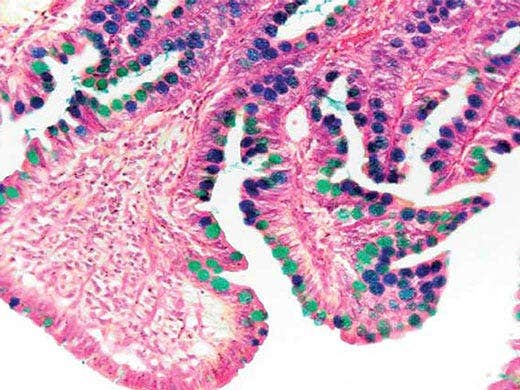

Probe: Darm